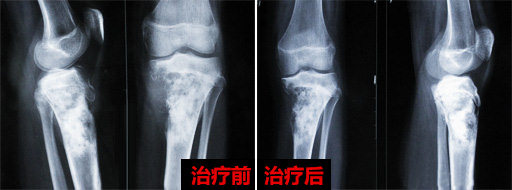

2014年4月15号,我们来到广州中医药大学金沙洲医院国际肿瘤中心,挂到了医院肿瘤科擅长热疗的胡群峰主任的号,主任在看过我的CT与 MRI等所有资料之后,给我的建议是采用热疗联合化疗药物介入,化疗药物的用量仅仅是单一化疗最小药量的1/10,副作用只有微乎其微,而热疗是没有任何副作用的。

2014年4月27号,我做完了所有的治疗,人比以前的状态好了很多,也没有其他不适,只有按压时有些疼痛,出院前胡主任还特地嘱咐我平时饮食作息要注意的大小事项。胡主任的暖心与随和让我真的始料未及,并不像其他医院的医生那样的冷冰冰对待我。

2014年12月我再到医院复查,以前建议我手术的医生问我最近是用什么治疗,恢复的那么好。我说我是用了化疗,他有点不太相信,觉得化疗的药量我那身体应该也接受不了。确实是这样,我是接受了小剂量的化疗药物与热疗,跟单独化疗还是有些区别,出门的时候看着以前医院病友那光秃秃的头,苍白的脸色,如果当时的我再次手术,估计也还是起不了床吧。为什么大部分肿瘤病人手术、化疗、放疗后会出现复发转移